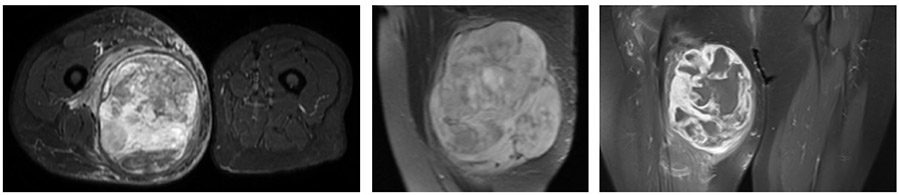

VAKA 5: Uyluk Yerleşimli Miksofibrosarkom

Uyluk bölgesinde şişlik ile bize başvuran ve yapılan iğne biyopsisinde yumuşak doku sarkomu (Miksofibrosarkom) tanısı konulup radyoterapiyi takiben tümörü temiz bir şekilde çıkarılan hastamız

Ameliyat Öncesi: MR’da uyluk iç kısımda sınırları düzensiz, heterojen yumuşak doku kitlesi ve çevreleyen ödem görülmekte